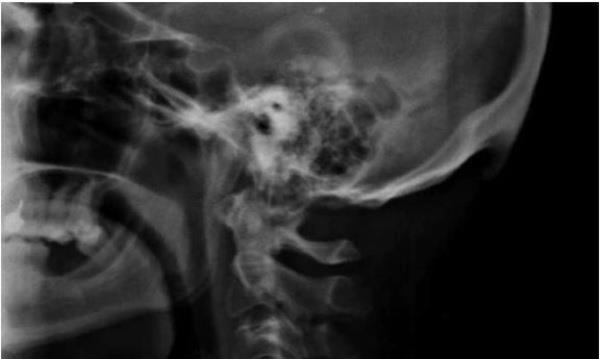

2. Avustralya’daki Sunshine Coast Üniversitesi’den bilim adamları Dr. David Shahar ve Prof. Mark Sayers, 18-30 yaş arasındaki 218 kişinin röntgen çekimlerini inceledi. Yapılan araştırmalar sonucu röntgen çekilen kişilerin neredeyse yarısının kafatası şeklinin yoğun cep telefonu ve tablet kullanımına bağlı olarak ‘değiştiği’, boynuzumsu bir çıkıntıya benzediği belirtildi.

Avustralya’daki Sunshine Coast Üniversitesi’den bilim adamları Dr. David Shahar ve Prof. Mark Sayers, 18-30 yaş arasındaki 218 kişinin röntgen çekimlerini inceledi. Yapılan araştırmalar sonucu röntgen çekilen kişilerin neredeyse yarısının kafatası şeklinin yoğun cep telefonu ve tablet kullanımına bağlı olarak ‘değiştiği’, boynuzumsu bir çıkıntıya benzediği belirtildi.

3. Yapılan araştırmaya göre, gününün büyük kısmında teknolojik aletlere kafasını eğerek bakan gençlerin, kafatasındaki oksipital kemik denen bölge, görünür şekilde belirginleşmeye başlıyor.

Yapılan araştırmaya göre, gününün büyük kısmında teknolojik aletlere kafasını eğerek bakan gençlerin, kafatasındaki oksipital kemik denen bölge, görünür şekilde belirginleşmeye başlıyor.

6. Ensenin üstünde sivrilen 10-30 milimetre arasında değişen çıkıntıya, &#8216;dış oksipital kabartı&#8217; deniyor. Dış oksipital kabartıya, taşınabilir dijital cihazlar yaygınlaşmaya başlamadan önce daha çok yaşlı insanlarda rastlandığı, gençlerde ise oldukça nadiren rastlandığı belirtiliyor.

Ensenin üstünde sivrilen 10-30 milimetre arasında değişen çıkıntıya, ‘dış oksipital kabartı’ deniyor. Dış oksipital kabartıya, taşınabilir dijital cihazlar yaygınlaşmaya başlamadan önce daha çok yaşlı insanlarda rastlandığı, gençlerde ise oldukça nadiren rastlandığı belirtiliyor.